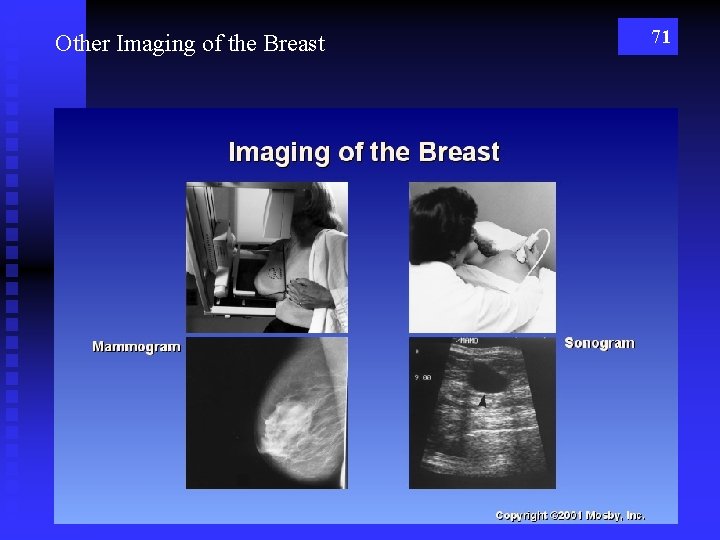

Other Imaging of the Breast 71